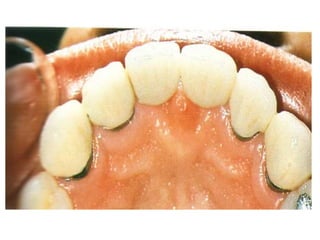

*Jacket crown: it is a

non metallic, full

coverage restoration

(porcelain) that rebuilds

the prepared clinical

crown of the anterior

teeth and restores it

esthetically and

functionally.